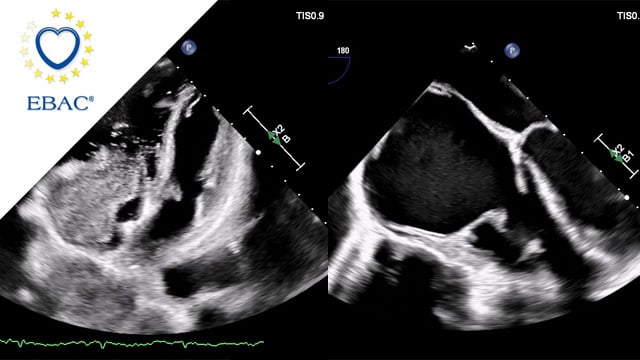

How should I treat this aortic stenosis with small anatomy, low coronary offset and extremely horizontal aorta

An 81-year-old patient with symptomatic severe aortic stenosis, a 74° horizontal aorta, and critically low coronary height—a challenging mix that pushed the heart team to weigh all procedural options. Discover how detailed CT analysis, intra-procedural strategy, and step-by-step imaging assessments guided their approach. What would you...